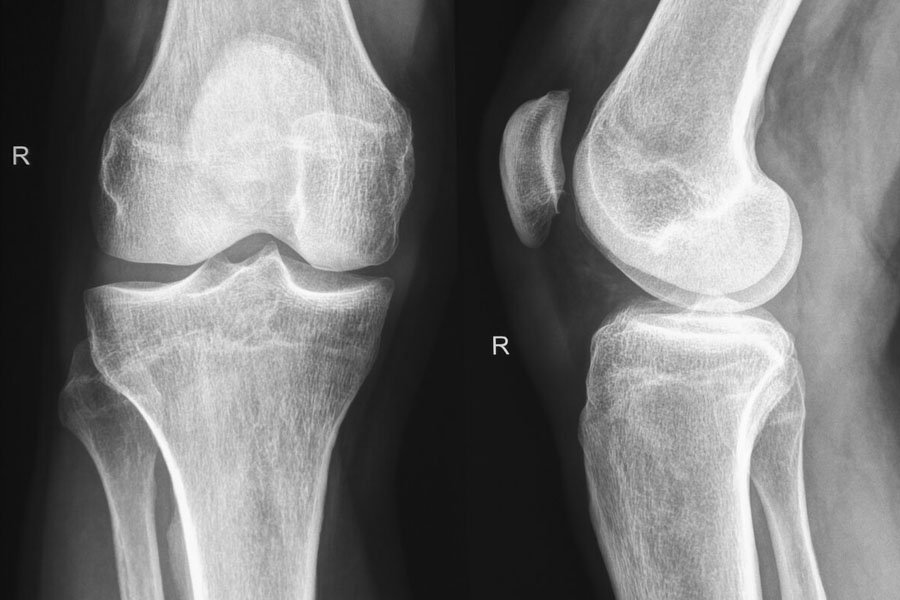

RX Ginocchio

è un esame rapido e di facile esecuzione indicato nella ricerca di lesioni traumatiche, artrosi o alterazioni morfologiche a carico di una o più componenti articolari.